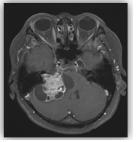

신경초종은 신경세포를 둘러싸고 있는 슈반세포에서 기원한 종양이며, 뇌와 척수에서 모두 발생할 수 있습니다. 이 중 두개강 내에 8번 뇌신경에서 발생하는 신경초종을 청신경초종이라고 합니다. 초기에는 내이도 내에서 발견되고 종양이 커지면서 내이도가 확장되고 다양한 방향으로 자라나 주위 뇌신경, 뇌간, 및 소뇌를 압박하여 여러 신경학적 증상을 유발합니다. 발생 빈도는 원발성 두개강 내 종양의 6~9% 정도이고 두개강 내에 발생하는 신경초종의 90%이상을 차지합니다. 주로 30세 이후의 성인에서 발생하며 여성이 남성보다 2배 정도 발생률이 높다고 알려져 있습니다. 20세 미만에서는 제2형 신경섬유종증 환자에서 양측성으로 주로 발생합니다. 청신경초종은 95% 이상이 편측성으로 발생하고, 이 경우 비유전적으로 발생합니다. 약 5%이하에서 양측성으로 발생하는 경우가 있는데 이는 제2형 신경섬유종증과 연관되어 있을 가능성이 높습니다. 제2형의 신경섬유종증은 제1형 신경섬유종증에 비해 아주 드물게 발생하는데 양측에 발생한 청신경초종 또는 청신경초종이 동반된 다발성 뇌척수 수막종, 성상 세포종, 상의 세포종 등이 주로 발생하는 것으로 알려져 있습니다.